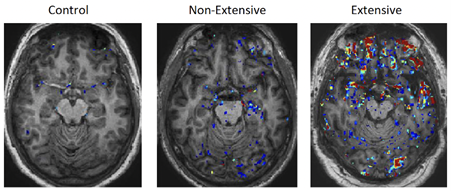

A comparison of the MRI brain scans of people in different cohorts. Left: Control (normal MRI brain scan); Middle: Non-extensive (red/blue pixels showing non-extensive leakage of the BBB); Right: Extensive (red pixelation showing extensive BBB leakage in a retired symptomatic individual). Image: Prof. Matthew Campbell et al. Trinity College Dublin.

By using advanced MRI scans on retired rugby players and boxers and cross-referencing data obtained in post-mortem brain tissue from athletes diagnosed with Chronic Traumatic Encephalopathy (CTE), the team discovered that this leakage allows inflammatory proteins to seep into the brain. These inflammatory proteins then trigger a cascade of damage, including the build-up of p-Tau, a toxic protein associated with Alzheimer’s Disease and other forms of dementia.

“We found that retired athletes with the most extensive ‘leakage’ in their brain barrier also scored significantly lower on cognitive tests, specifically those measuring memory and executive function.”